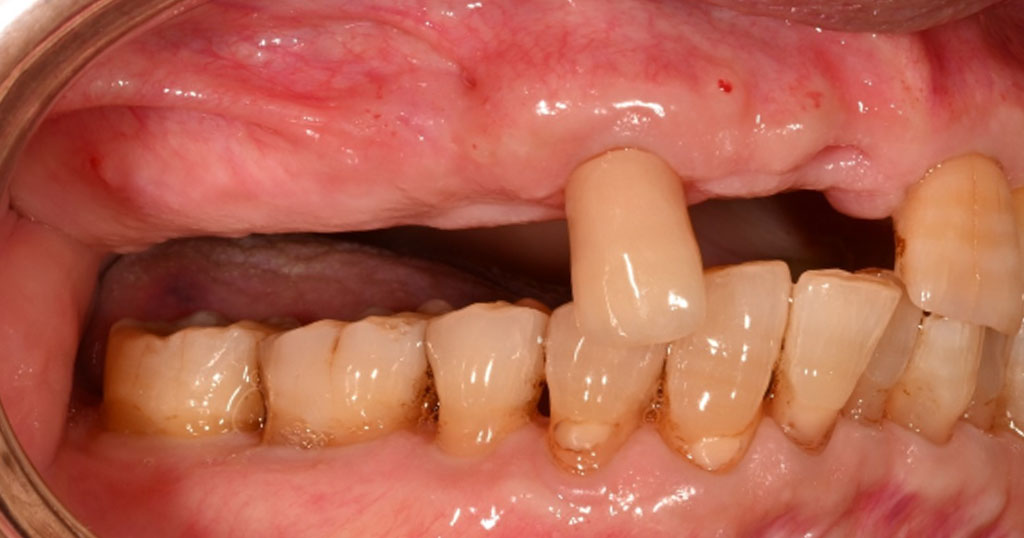

Before2

80代男性。上顎右124567番が欠損した状態で来院。今まで使用していた保険の入れ歯を使用しているが不満で、インプラント手術も怖いということで自費の入れ歯をご希望とのこと。

金属部分がない、フィット感がある、入れ歯を支える歯への負担を軽減させるため、上顎右124567番の欠損を補う着脱が簡単なコンティースを作成